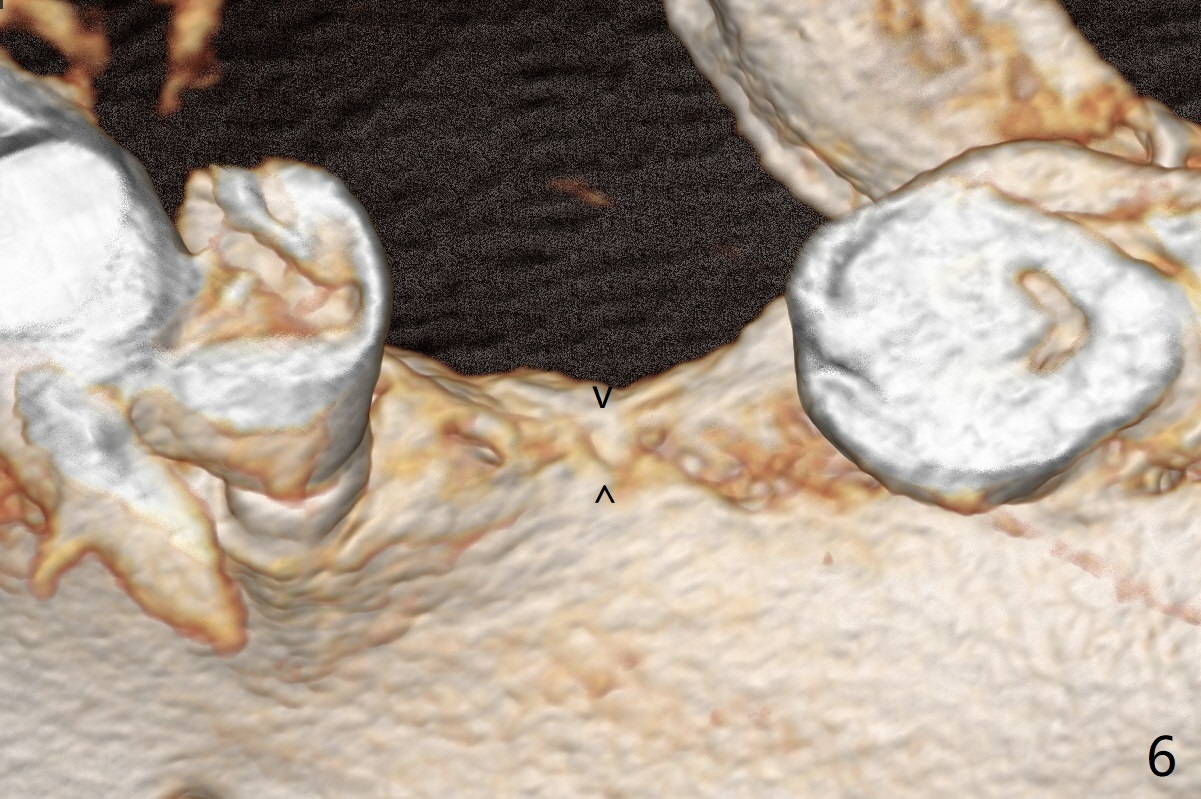

56岁男,高血压,紧张怕痛,要求迅速手术,所以我们初步选择导航。由于他还能在右边咀嚼,先做左侧植牙。左侧好像缺失两个牙齿(图一),不过近远中间隙更象缺失一个牙齿(图二)。牙槽嵴狭窄,骨皮质厚,容易植骨吗?还是容易劈开?牙槽嵴狭窄(图三,四,六)似乎适合种植两个小植体(两个双尖牙)。如果只植入一个,牙槽骨高度差些,植体短(图五),仿佛做牙槽嵴劈开术比较好。